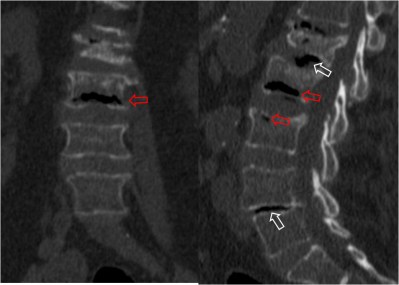

SIGNO DE LA DOBLE LÍNEA

Signo de osteonecrosis avascular visible en la resonancia magnética, en imágenes potenciadas en T2. En la osteonecrosis avascular se ve una línea de alta intensidad de señal rodeada por un anillo paralelo de hiposeñal, con frecuencia de bordes serpiginosos. La línea hiperintensa (flecha negra) corresponde a tejido de granulación hiperémico y la línea externa hipointensa (flecha roja) corresponde a hueso escleroso.

Otro ejemplo en un paciente con infartos óseos múltiples en fémur distal y tibia proximal.